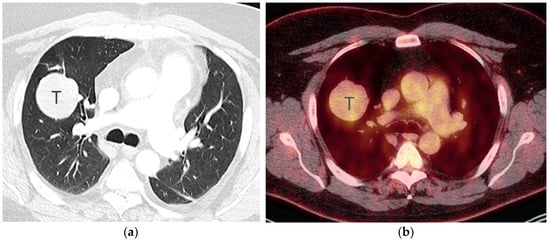

6. PET/CT for Lung Cancer